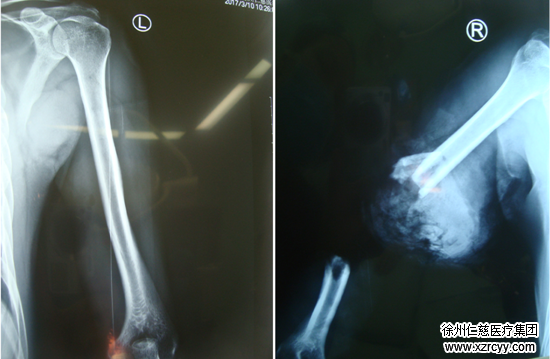

术前检查

黎医生介绍“探查发现患者右上臂中段完全离断、磋商比较严重,肱骨粉碎性骨折、骨片游离,肱动脉及伴行静脉、头静脉残端挫伤。同时,由于创口遭受到了挤压,断端血管、神经碾挫较重,情况非常严重,需要立即实施清创和断肢再植”。